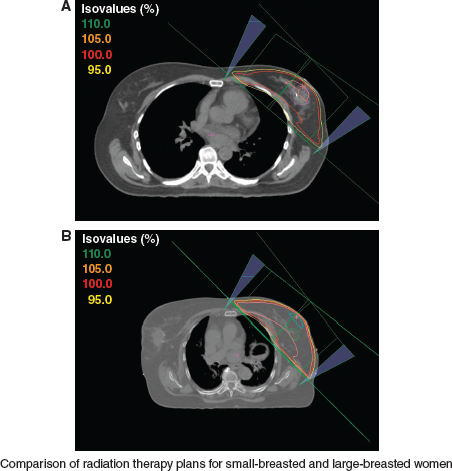

Techniques to deliver breast radiotherapy can differ, depending on the size of the breast. A and B both show radiation fields for patients who have tangents with standard, fixed-angle wedges. The isodose values on the left of each image correspond to the percentage of the prescribed dose. Lines of the same color on the CT simulation axial slice show the corresponding dose distribution in the breast tissue. B demonstrates that in a large-breasted patient, the 105% isodose covers a larger volume of breast tissue, whereas A reveals that the 110% isodose is not present at all in the smaller-breasted patient. An increased-dose inhomogeneity is inherent for larger-breasted patients, because it is affected by the size and shape of the breast and by the separation distance across the posterior field edge from the medial to the lateral field border. A larger breast size or a larger separation, especially more than 25 cm, results in greater dose inhomogeneity in the treatment volume. Homogeneity within 7% to 10% of the prescribed dose is desirable.